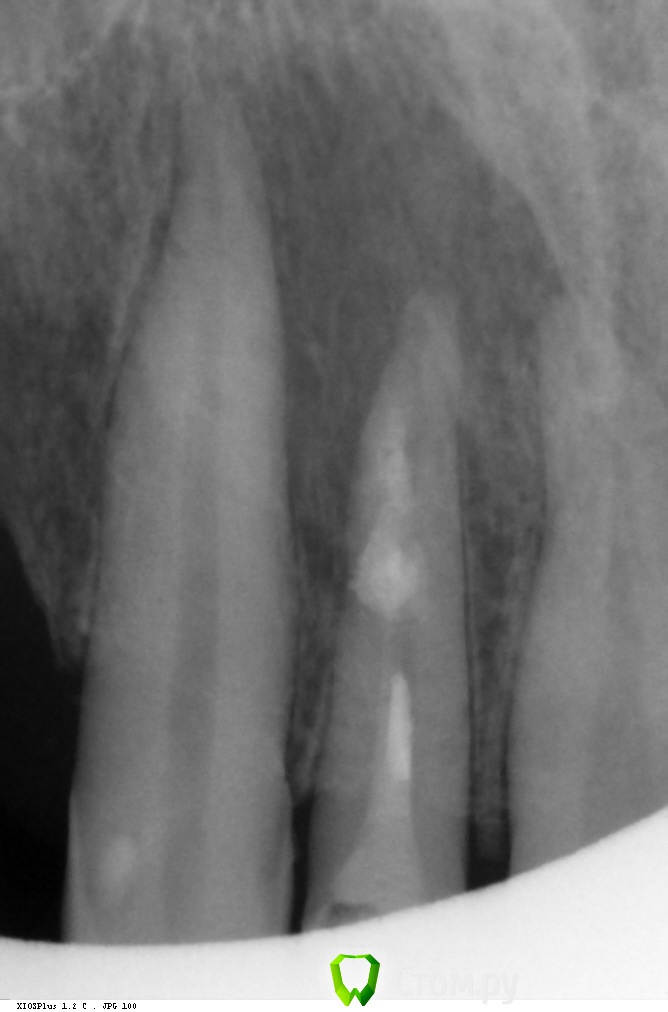

Каплан Опубликовано 30 января, 2014 Автор Поделиться Опубликовано 30 января, 2014 внутренняя резорбция. пока что без перфорации... (ап.лок работал без искажений) Ссылка на комментарий

Kivilgar Опубликовано 30 января, 2014 Поделиться Опубликовано 30 января, 2014 внутренняя резорбция. пока что без перфорации...тоже так думаю Ссылка на комментарий